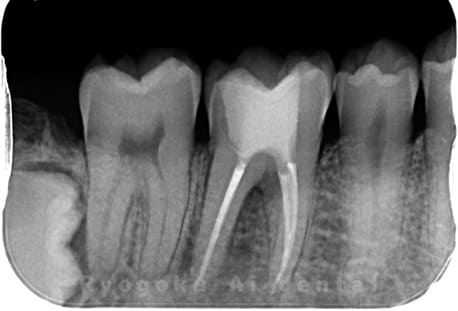

Case08

- 原因

- 慢性根尖性歯周炎

- 治療内容

- マイクロエンド

- 治療費用

- 121,000円

左下が腫れているとのことで来院された患者さんです。根の先に病気を作っているため、マイクロスコープを使用した治療を提案し、進めていきました。現在も経過良好です。

<リスク・副作用>

術後は痛み、腫れ、痺れなどの副作用が生じる場合があります。症状が再発する可能性があります。